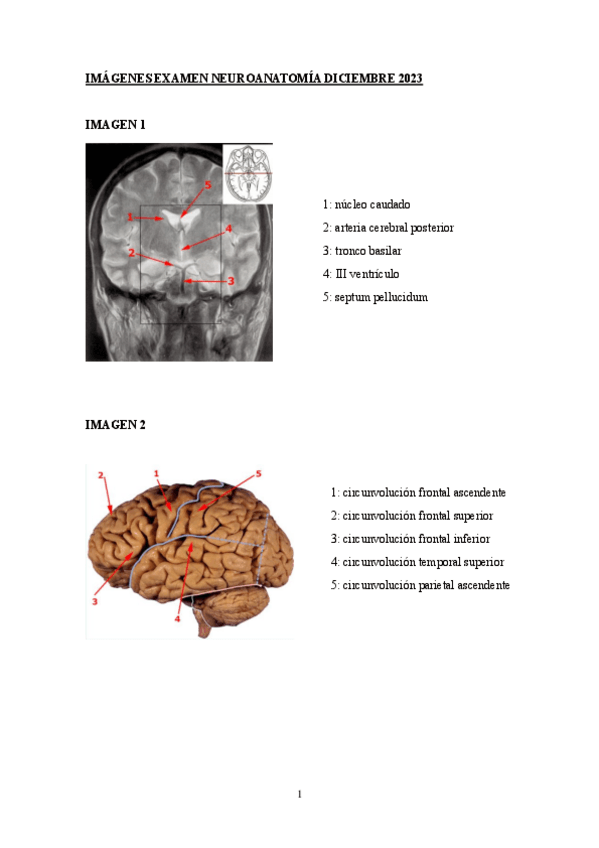

EXAMEN NEUROANATOMÍA DICIEMBRE 2023

He publicado nuevos apuntes de 2º Anatomía Humana: Estesiología y Sistema Nervioso: EXAMEN NEUROANATOMÍA DICIEMBRE 2023

PREGUNTAS-CORTAS-EXAMEN-NEUROANATMIA-DICIEMBRE-2023.pdf

IMAGENES-EXAMEN-NEUROANATOMIA-DICIEMBRE-2023.pdf

CASOS-CLINICOS-EXAMEN-NEUROANATOMIA-DICIEMBRE-2023.pdf